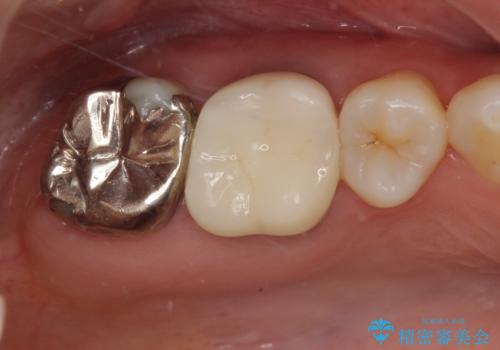

適合もよく、機能的に問題もなく、見た目も満足されていました。

今後はメンテナンスで通ってもらいながら、ほかの部位の金属の詰め物が気になったらセラミッククラウンに変えていく予定です。